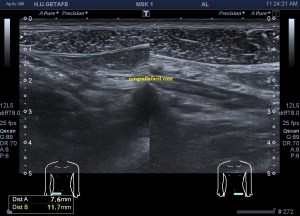

Dirigí el estudio a la pared abdominal y a los rectos anteriores. En este caso es muy importante conocer la anatomía regional. Os la enlazo para que la puedas estudiar, pero en resumidas cuentas debemos tener claro que esta musculatura abdominal anterior tiene 3 bloques bilaterales que ocupan epigastrio y mesogastrio y por debajo de la región umbilical otro bloque muscular que termina en la sínfisis púbica.

Durante la exploración se valoró la región de sospecha en mesogastrio izquierdo observando normalidad ecográfica, por contra, su lado contralateral me sorprendió presentándose como una estructura muscular anómala, hiperecogénica, atrófica con respecto al lado izquierdo.

La imagen 1 es la ecografía anatómica que buscamos, los rectos anteriores a ambos lados de la imagen simétricos de aspecto hipoecogénico.

De la imagen 2 a 5 puedes ver los cuatro paquetes musculares pares que conforman la cara anterior del abdomen, lo que todos identificamos en esos cuerpos esculturales como la «tableta de chocolate». Cuando lo ecografiamos son igual de «sexys» si me permites la expresión, porque son muy bonitos, al ser simétricos su estudio es muy agradecido.

En la imagen 2 podemos ver el primer grupo muscular de los rectos abdominales donde ya observas como el lado derecho es ligeramente más pequeño que su lado izquierdo aunque la ecogenicidad es idéntica.

En la imagen 3, segundo grupo muscular, puedes ver como el lado izquierdo es normal y el derecho está completamente atrófico tanto ecográficamente, como visualmente, como al tacto, por tanto, la sospecha del médico no era más que la normalidad en el lado izquierdo y el aspecto atrófico del lado derecho.

En la imagen 4, correspondiente con el tercer grupo muscular, ambos músculos tienen semiología ecográfica similar a excepción de su tamaño, que es reducido en el lado derecho…

El último grupo muscular, imagen 5, alargado y que termina por insertar en la sínfisis púbica, es de aspecto rigurosamente normal, ecográficamente isoecogénico y simétrico de tamaño.

La imagen 6 y 7 es el detalle del segundo grupo muscular de los rectos anteriores para que observes las diferencias entre ambos y puedas valorar ambas semiologías.

En esta ocasión, lo destacable es que la normalidad era lo que a la palpación era sospechoso y que el lado derecho, que parecía normal a la exploración, era el patológico ecográficamente. Llama la atención como todo el grupo muscular derecho está disminuido de tamaño a expensas de una atrofia en el vientre del músculo, que se hace muy evidente en el segundo grupo muscular.